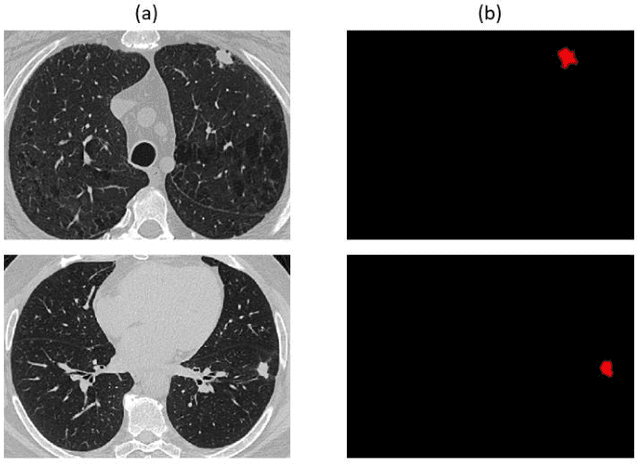

Abstract:Non-small cell lung cancer (NSCLC) is a serious disease and has a high recurrence rate after the surgery. Recently, many machine learning methods have been proposed for recurrence prediction. The methods using gene data have high prediction accuracy but require high cost. Although the radiomics signatures using only CT image are not expensive, its accuracy is relatively low. In this paper, we propose a genotype-guided radiomics method (GGR) for obtaining high prediction accuracy with low cost. We used a public radiogenomics dataset of NSCLC, which includes CT images and gene data. The proposed method is a two-step method, which consists of two models. The first model is a gene estimation model, which is used to estimate the gene expression from radiomics features and deep features extracted from computer tomography (CT) image. The second model is used to predict the recurrence using the estimated gene expression data. The proposed GGR method designed based on hybrid features which is combination of handcrafted-based and deep learning-based. The experiments demonstrated that the prediction accuracy can be improved significantly from 78.61% (existing radiomics method) and 79.14% (deep learning method) to 83.28% by the proposed GGR.